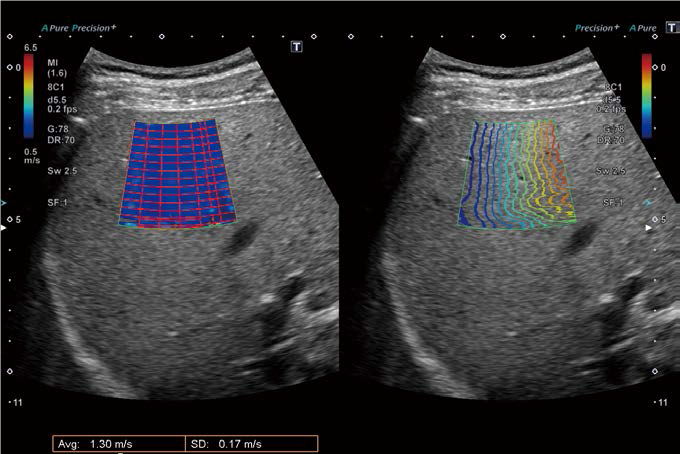

Advanced SWE

Aplio a містить ряд передових програм, успадкованих від Aplio i800, таких як Shear Wave Elastography (SWE), Superb Micro-vascular Imaging (SMI) і Protocol Assistant . Зокрема, SWE дозволяє кількісно аналізувати жорсткість тканин шляхом вимірювання швидкості поширення зсувної хвилі.

Це надзвичайно корисно для оцінки тяжкості фіброзних змін, що є основним фактором у визначенні прогнозу пацієнтів із захворюваннями печінки (рис. 3).

Коли ожиріння печінки прогресує до цирозу, кількість жиру фактично зменшується, що може помилково вважатися ознакою клінічного поліпшення. Ось чому важливо оцінити жорсткість тканини печінки за допомогою SWE. У Aplio a ATI (для вимірювання жирових змін) і SWE (для вимірювання фіброзних змін) можна виконати за допомогою однієї кнопки, і немає необхідності змінювати датчики.

Цей метод візуалізації, відомий як Advanced SWE, є оригінальною технологією, розробленою Canon,  яка дозволяє одночасно оцінювати жирові та фіброзні зміни в цільовій області (рис. 4).